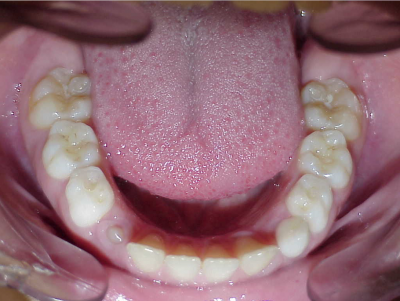

Voor behandeling